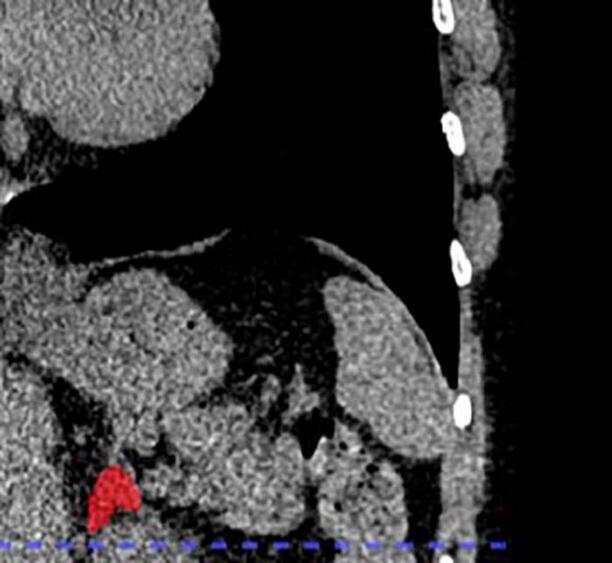

Врачи из Университета Джонса Хопкинса на конгрессе RSNA 2025 представили первый в мире визуальный биомаркер хронического стресса. Он позволяет буквально увидеть, как годы напряжения «разъедают» организм изнутри, причем увидеть это можно на обычных КТ-снимках грудной клетки, которые миллионы людей делают каждый год по любому поводу.

Взяли базу данных проекта MESA — одного из самых долгосрочных исследований атеросклероза в США. 2842 человека среднего возраста 69 лет, половина женщин. За участниками наблюдали 10 лет и фиксировали инфаркты, инсульты, сердечную недостаточность и смерть.

Обычный анализ на кортизол показывает только «сиюминутную картинку». Утром может быть высокий, вечером низкий, после кофе — скачок. А объем надпочечников — это как годовые кольца на дереве: он отражает, сколько лет человек провел в состоянии «бей или беги».

«До сих пор у нас не было способа измерить и количественно оценить кумулятивный эффект хронического стресса, кроме анкет и косвенных маркеров. Впервые мы можем „увидеть“ долгосрочное бремя стресса внутри организма, используя сканирование, которое пациенты уже проходят ежедневно», — говорит старший автор Шадпур Демехри.